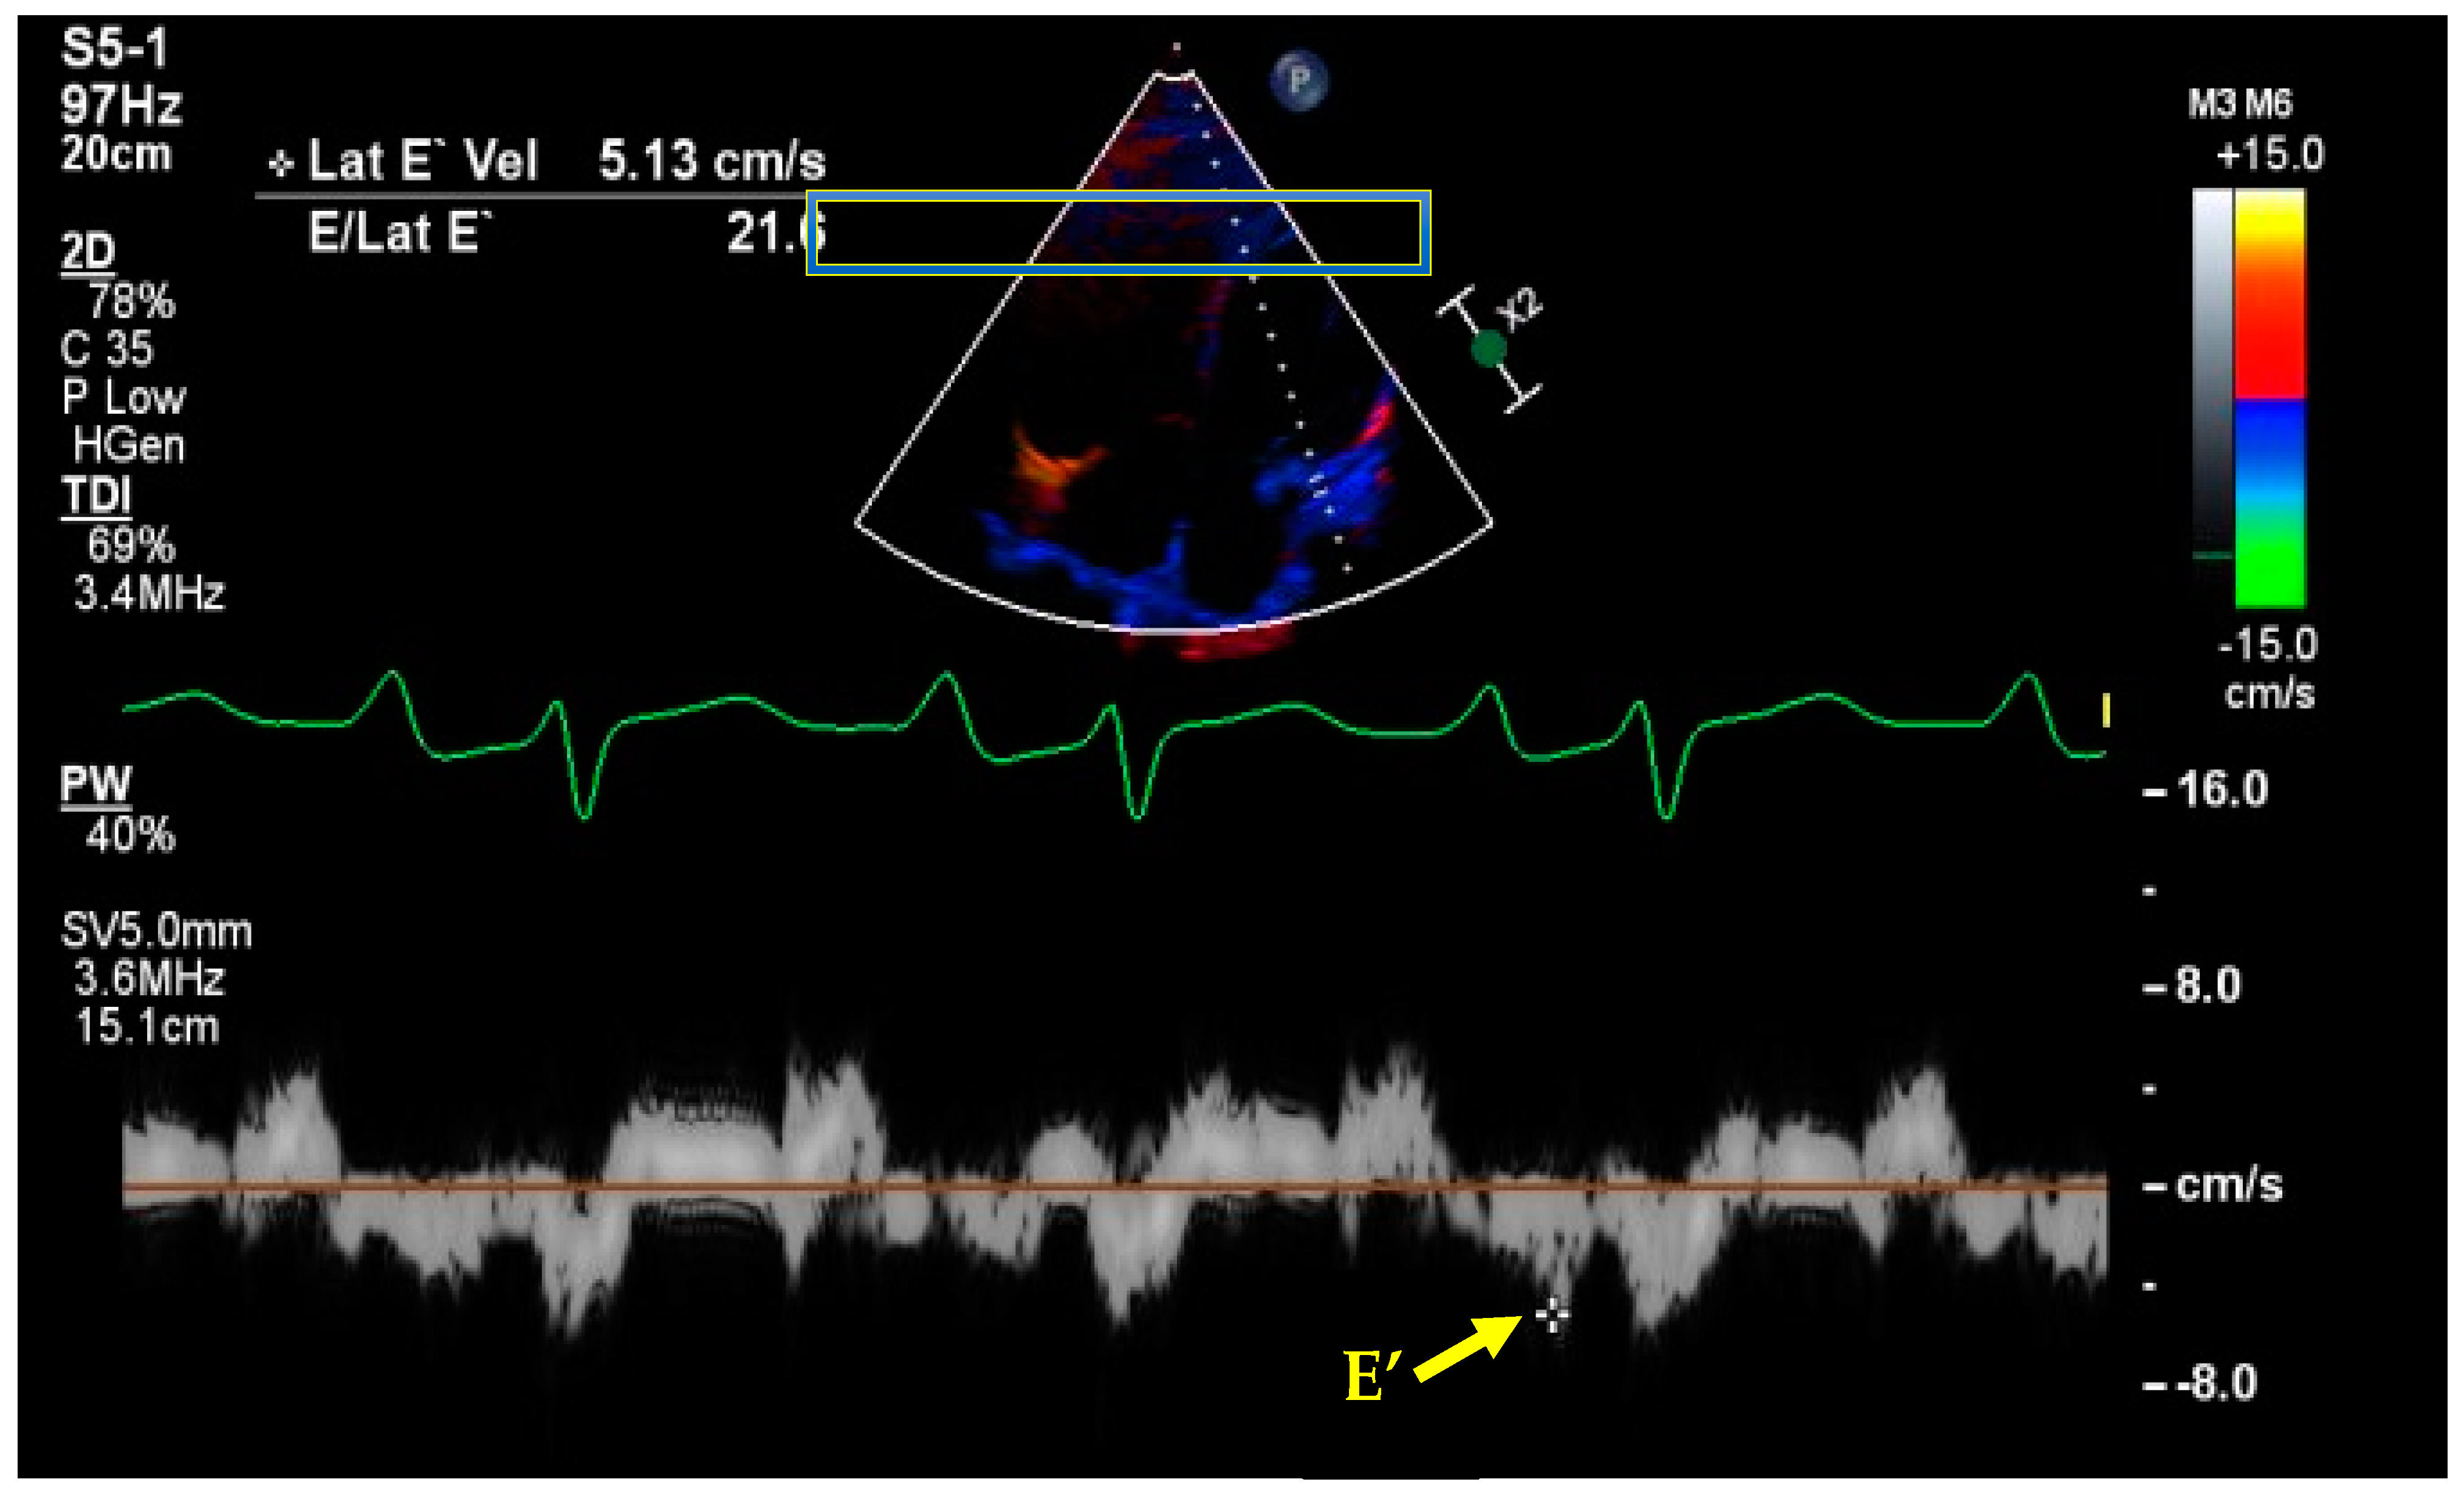

7. Basic and Advanced Echocardiography

- Kim, J.S.; Yang, J.W.; Yoo, J.S.; Choi, S.O.; Han, B.G. Association between E/e ratio and fluid overload in patients with predialysis chronic kidney disease. PLoS ONE 2017, 12, e0184764. [Google Scholar] [CrossRef] [PubMed]

- Nagueh, S.F.; Middleton, K.J.; Kopelen, H.A.; Zoghbi, W.A.; Quinones, M.A. Doppler tissue imaging: A noninvasive technique for evaluation of left ventricular relaxation and estimation of filling pressures. J. Am. Coll. Cardiol. 1997, 30, 1527–1533. [Google Scholar] [CrossRef]

- Nagueh, S.F.; Smiseth, O.A.; Appleton, C.P.; Byrd, B.F., 3rd; Dokainish, H.; Edvardsen, T.; Flachskampf, F.A.; Gillebert, T.C.; Klein, A.L.; Lancellotti, P.; et al. Recommendations for the Evaluation of Left Ventricular Diastolic Function by Echocardiography: An Update from the American Society of Echocardiography and the European Association of Cardiovascular Imaging. J. Am. Soc. Echocardiogr. 2016, 29, 277–314. [Google Scholar] [CrossRef]

- Denault, A.Y.; Langevin, S.; Lessard, M.R.; Courval, J.F.; Desjardins, G. Transthoracic echocardiographic evaluation of the heart and great vessels. Can. J. Anaesth. 2018, 65, 449–472. [Google Scholar] [CrossRef]

- Arbo, J.E.; Maslove, D.M.; Beraud, A.S. Bedside assessment of right atrial pressure in critically ill septic patients using tissue Doppler ultrasonography. J. Crit. Care 2013, 28, e1111–e1115. [Google Scholar] [CrossRef]